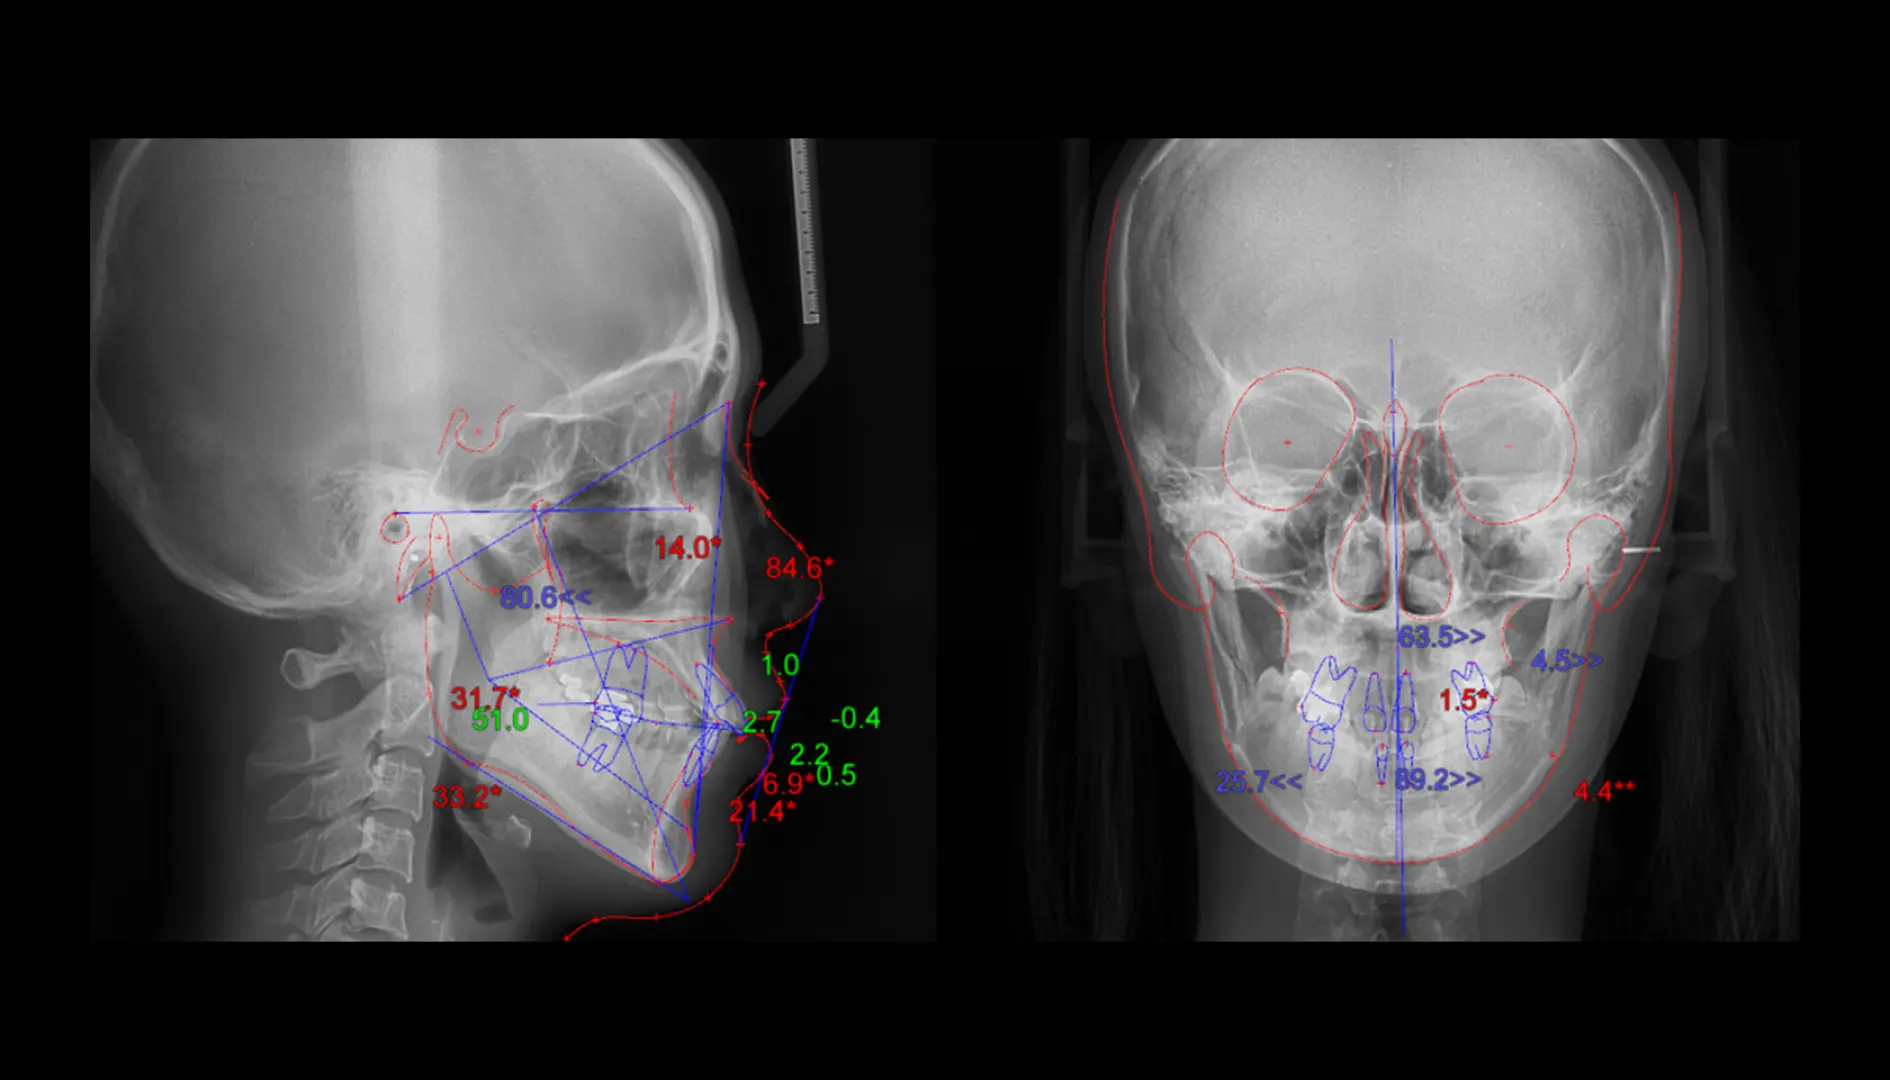

디지털 분석 (측면 & 정면)치과 교정 및 악안면 수술을 위한 디지털 분석

유저가 커스텀 요청한 분석 차트 형태로 분석 결과를 확인(Analysis Wizard)